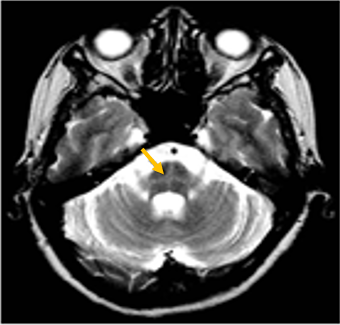

진행 핵상 마비는 대표적인 파킨슨 증후군 중의 하나입니다. 파킨슨병과 다른 점은 질병의 초기부터 중심을 잡기 어려운 체위 불안정이 나타나 자주 넘어진다는 것입니다. 파킨슨병의 경우 질병이 상당히 진행된 뒤에 체위 불안정이 나타납니다. 또한 진행 핵상 마비에서는 목 주위 근육을 비롯한 몸 중심 근육의 경축이 나타나, 목을 뒤로 젖히면서 걷는 모습이 보입니다. 그리고 눈의 운동을 조절하는 기능에 장애가 나타나 아래쪽을 바라보는 데 문제가 생겨 계단을 내려갈 때 어려움을 겪는 경우가 많습니다. 진행 핵상 마비가 의심되는 경우, 뇌 자기공명영상(MRI)에서 중뇌의 위축이 비정상적으로 심하게 나타나는 소견을 확인하거나, 뇌포도당 양전자 단층촬영(PET)에서 전두엽과 중뇌의 대사 기능이 저하된 소견을 확인하여 진단에 참고할 수 있습니다.

[진행핵상마비 환자의 뇌자기공명영상에서 확인되는 중뇌 위축 소견]

[진행핵상마비 환자의 뇌포도당 양전자 단층 촬영에서 확인되는 중뇌의 대사 저하 소견]